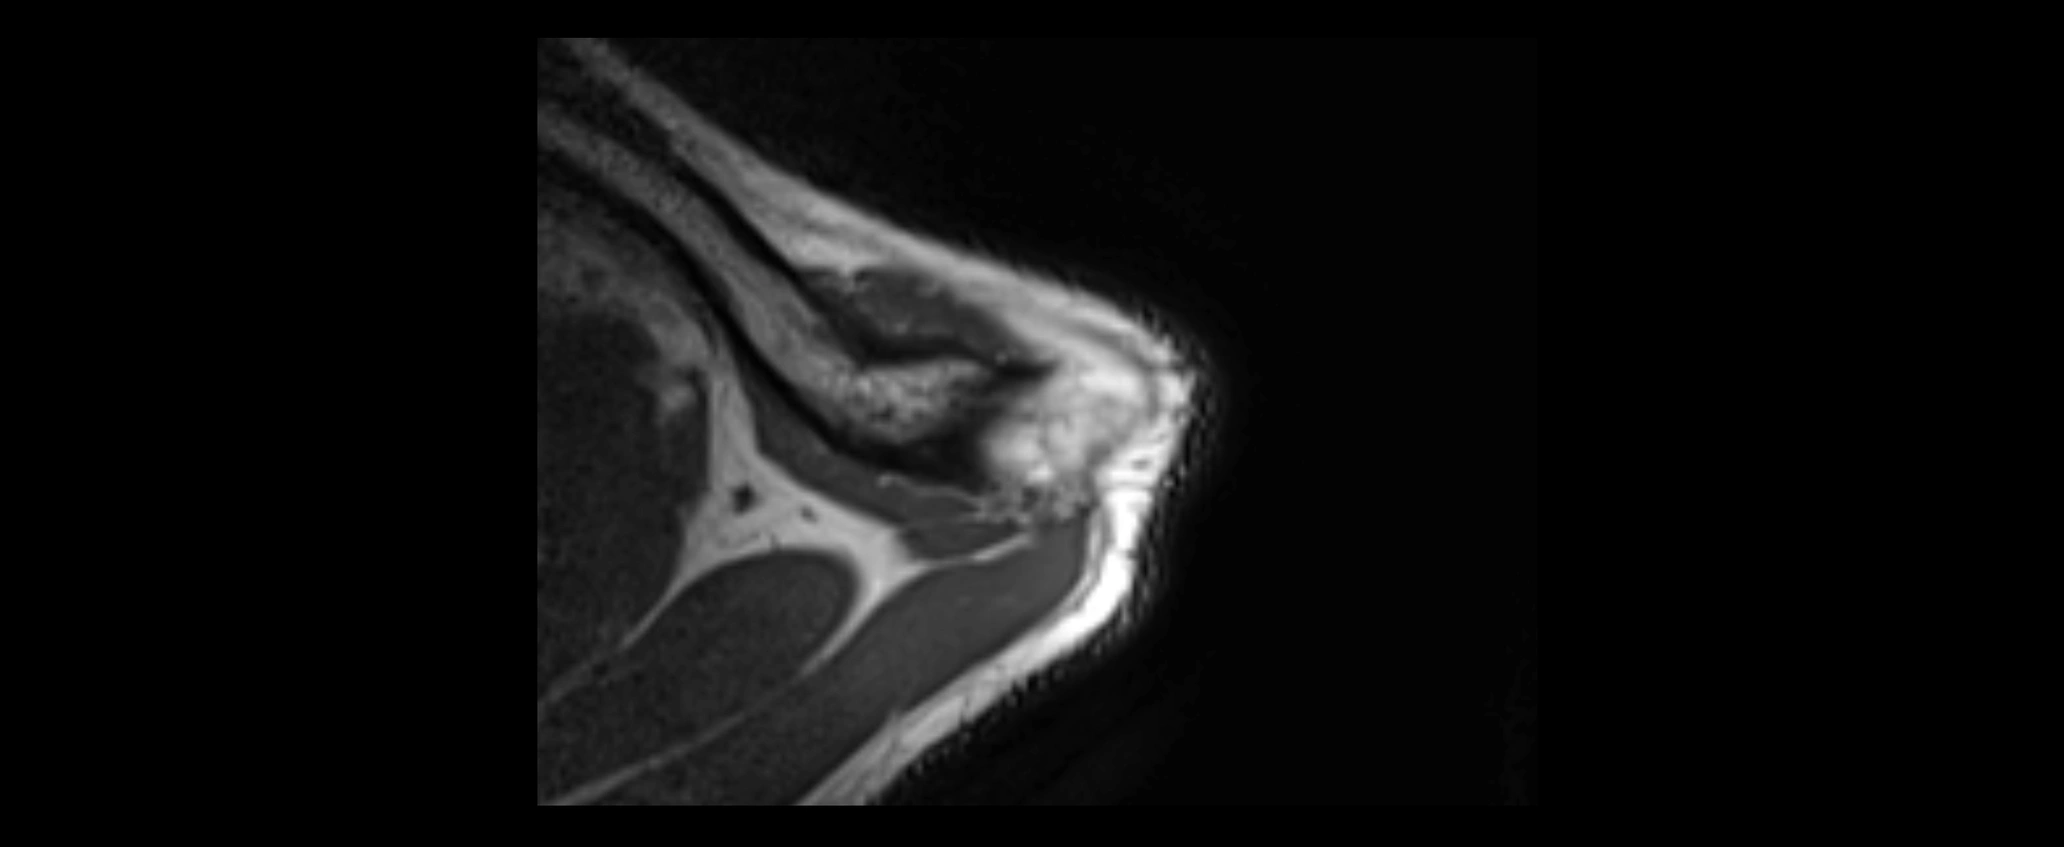

MRI images

image